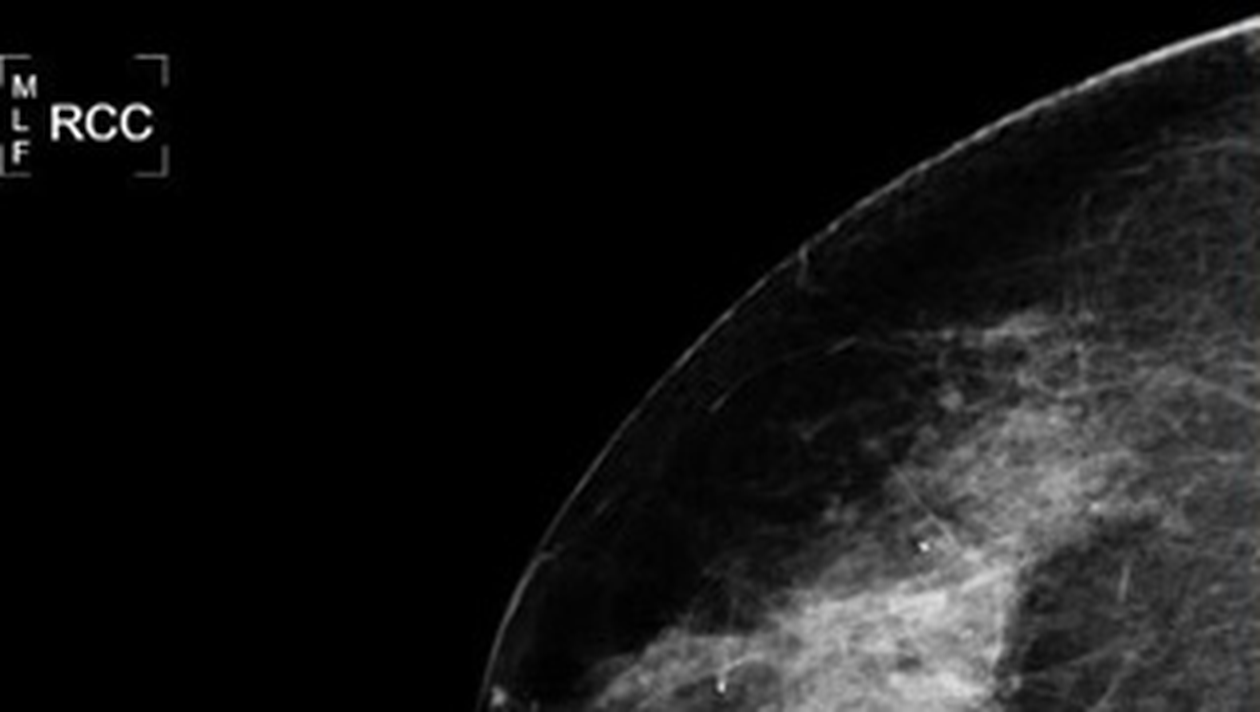

Mamografie realizata intr-un cabinet medical

NASA vrea sa dovedeasca utilitatea tehnologiei pe care o are la dispozitie, ajutand medicii sa descopere cancerul in stadiu incipient, prin efectuarea unor mamografii performante.

Programul spatial americanfoloseste un soft, numit MED-SEG, pentru a efectua mamografii al caror scop este descoperirea cancerului in stadiu incipient.

Doctorului Thomas Rutherford, directorul clinicii de ginecologie-oncologie a Universitatii Yale, crede ca folosirea acestei tehnologii poate reduce incidenta „erorii umane” in timpul diagnosticarii pe baza evaluarii ecografiilor si radiografiilor, permitand depistarea celulelor maligne in stadiu incipient.